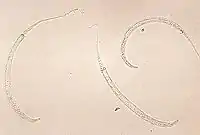

Збудник є гельмінтом (нематодою) ниткоподібної форми. Входить до порядку Spirurida, що включає також філярії Wuchereria bancrofti, Brugia malayi та Loa loa — збудників філяріїдозів. Самки Dracunculus medinensis завдовжки 30–120 см, при цьому завтовшки лише 1-2 мм, самці — 12–30 см. Колір гельмінтів білий. Дорослі особини паразитують в організмі людини, рідше — тварин (мавп, собак, котів). Самки ришти народжують личинок, яких ковтають прісноводні рачки-циклопи, що є проміжними хазяями інвазії. Вони стають заразними через 2 тижні (2 ліньки) всередині циклопів. За межами тіла людини личинки можуть жити до 3-х днів.[12] Протягом цього часу для їхнього виживання необхідно, аби їх з'їли водяні блохи.[2] Всередині водяної блохи личинка може жити до чотирьох місяців,[12]